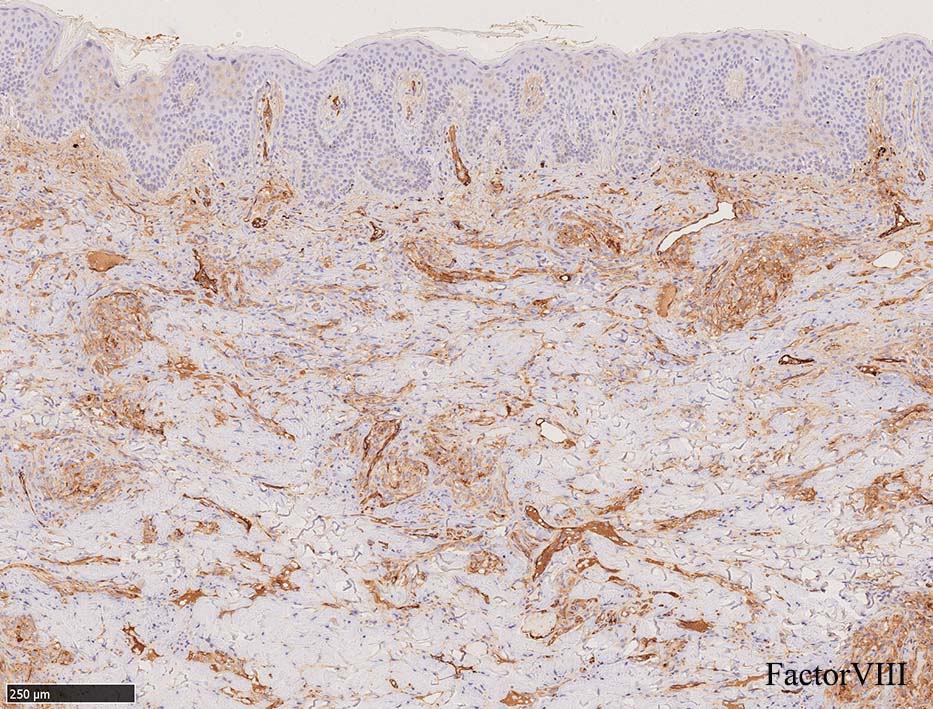

増生細胞はCd31, CD34, Factor Ⅷ, D2-40などが陽性を示す.

HHV-8の潜伏期関連抗原(HHV-8 Latency-associated nuclear antigen: HHV-8 LANA)が市販されており, 核が点状に染色される陽性所見がKaposi肉腫の確定診断に必須となっている.